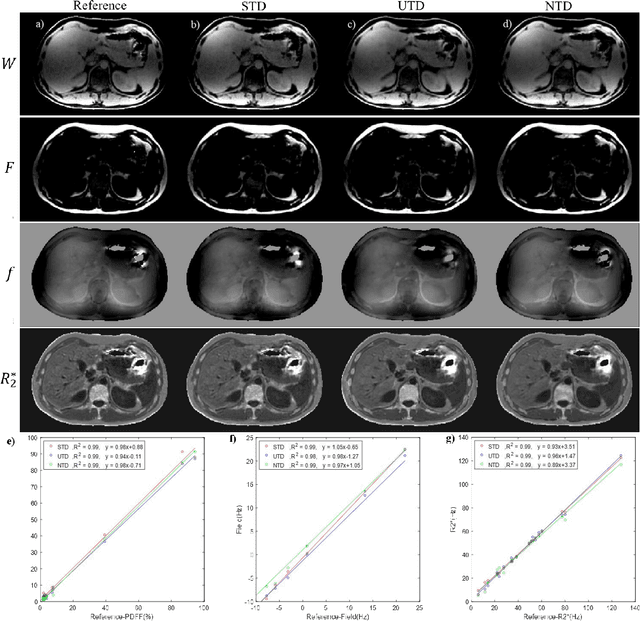

Abstract:Purpose: To use a deep neural network (DNN) for solving the optimization problem of water/fat separation and to compare supervised and unsupervised training. Methods: The current T2*-IDEAL algorithm for solving fat/water separation is dependent on initialization. Recently, deep neural networks (DNN) have been proposed to solve fat/water separation without the need for suitable initialization. However, this approach requires supervised training of DNN (STD) using the reference fat/water separation images. Here we propose two novel DNN water/fat separation methods 1) unsupervised training of DNN (UTD) using the physical forward problem as the cost function during training, and 2) no-training of DNN (NTD) using physical cost and backpropagation to directly reconstruct a single dataset. The STD, UTD and NTD methods were compared with the reference T2*-IDEAL. Results: All DNN methods generated consistent water/fat separation results that agreed well with T2*-IDEAL under proper initialization. Conclusion: The water/fat separation problem can be solved using unsupervised deep neural networks.